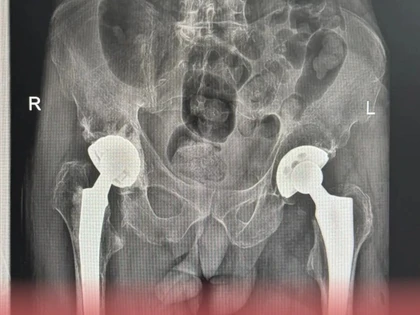

Их внедряют в местной Центральной городской больнице, где местные специалисты уже провели операции по эндопротезированию тазобедренного сустава при переломе шейки бедренной кости. Особенно внедрение новых технологий важно для людей старше 60 лет, которые часто падают в силу ухудшения возможностей координации, а это приводит к сложным переломам.

По данным Минздрава, на текущий момент в травматологическом отделении Ковровской ЦГБ уже установили более 10 эндопротезов тазобедренного сустава. Областные чиновники уверены, что перспективы развития данного направления в районной медицине выглядят обнадеживающе. Эндопротезирование тазобедренного сустава при переломах шейки бедра становится более доступным для пациентов, что значительно улучшает прогнозы лечения и реабилитации.